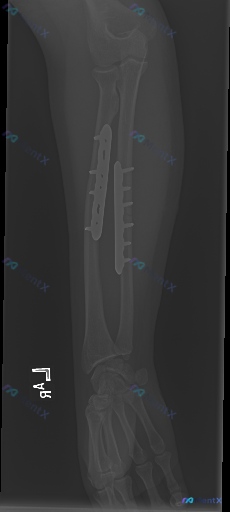

这张左前臂尺桡骨术后X光,除了已有的内固定,还有哪些值得警惕的异常?

基本背景:左前臂尺桡骨骨折术后复查

- 尺、桡骨干均有金属接骨板+多枚螺钉固定

- 骨折断端对位对线尚可,未见明确内固定松动、断裂或移位

- 骨折区域可见初步骨痂生长影

- 腕关节、可见的部分肘关节结构尚完整,关节间隙无明显狭窄/增宽

- 软组织轮廓清晰,未见明显肿胀或透亮区

- 除内固定外未见其他异常高密度影或病理性钙化

- 骨皮质密度尚可,未见明确广泛性骨质疏松或局限性骨质破坏